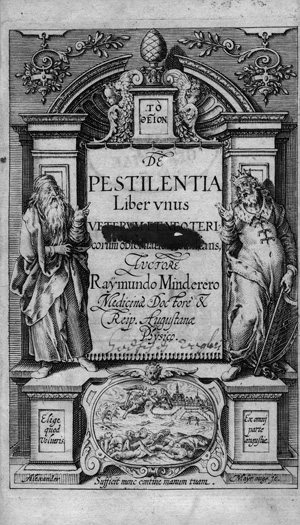

Minderer, Raimund

De Pestilentia liber unus. Veterum et neotericorum observatione constans

Nachverkaufspreis

400€ (US$ 455)